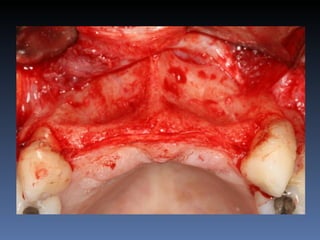

Diagnóstico: Desdentado parcial

pré-maxila.

Plano de tratamento: Reabilitação pré-maxila com

instalação de 2 implantes endo-ósseos (1.1,.2.2), para

reabilitação protética fixa.